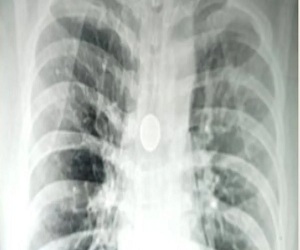

वाराणसी: अगर किसी शख्स की सांस नली में 25 पैसे का सिक्का पिछले 8 वर्षों से फंसा हो तो आप खुद समझ सकते हैं कि उसे किस तरह की परेशानियों से दो चार होना पड़ता होगा। लेकिन बनारस हिंदू विश्वविद्यालय (बीएचयू) के श्री सुंदरलाल अस्पताल के डॉक्टरों ने एक बेहद मुश्किल सर्जरी में एक 40 वर्षीय व्यक्ति की श्वास नली (श्वांस नली) में पिछले आठ वर्षों से फंसा 25 पैसे का सिक्का निकाला है। कार्डियो-थोरेसिक सर्जन प्रोफेसर सिद्धार्थ लखोटिया और प्रोफेसर एसके माथुर के नेतृत्व में डॉक्टरों की एक टीम ने मंगलवार को 20 मिनट तक चले ऑपरेशन में श्वास नली से सिक्का निकाला।

मरीज की सांस की नली से सिक्का निकालने में अहम भूमिका निभाने वाली एनेस्थिसियोलॉजी विभाग की डॉ. अमृता रथ ने कहा, “इस तरह के ऑपरेशन के लिए हाई लेवल की सटीकता की आवश्यकता होती है और थोड़ी सी भी गलती जीवन के लिए खतरा बन सकती है। सिक्के को निकालने के लिए एक एडवांस्ड रिजिड ब्रोंकोस्कोप का इस्तेमाल किया गया।”